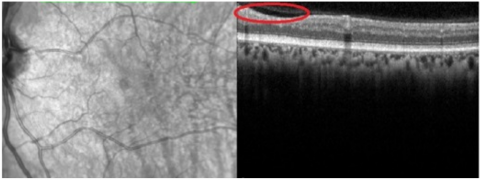

(a) sub-retinal detachment

(b) Macular edema

(c) Purtscher’s flecken

(d) Infected Purtscher’s retina analysis

Figure 8. Results of Purtscher’s Retinopathy analysis

When the OCT image exhibits extreme retinal distortion, artifacts, or noise, it is said to have the lowest performance. Dice coefficient < 0.60 and IoU < 0.50. The segmentation of anomalies and retinal layers by the model is not very accurate. Noise and artifacts can have a significant impact on predictions, resulting in a low overlap with the ground truth. In certain situations, the model is unable to offer meaningful diagnostic data. The spectral-domain optical coherence is shown in Figure 8. Left eye tomography shows a subfoveal neurosensory separation with rupture of the ellipsoid zone, along with significantly affected inner retinal areas and characteristic Purtscher Flecken (arrow).